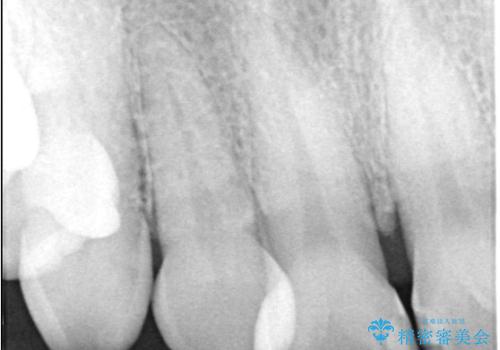

- 前歯の隙間とへこみが気になり、特に舌で触ると気になってストレスを感じるとのことで来院された患者様です。

上下ともに軽度の叢生があり、下顎がやや前突傾向にあったため、本来であれば矯正治療が第一選択となります。矯正によって下の前歯を後方に移動させることで、咬み合わせの改善とともに前歯のデコボコも整えることができます。

そのため今回は、右上2番を抜歯し、右上1番および左上1番をオールセラミッククラウンで審美的に修復しました。